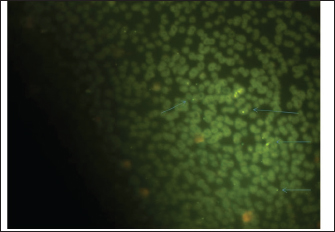

Fig. 2. Blood smear indicates Mycoplasma haemofelis invades equine RBCs. Fluorescent microscopy,0.1% acridine orange staining. 1000X. qPCR resultIn the current study, 79%(79/100) of diseased horses were found to be positive using qPCR (Figs. 3 and 4). The agreement between the two diagnostic methods was analyzed using Cohen's Kappa statistic. The observed agreement was 91% (91/100), and the expected agreement by chance was 72.04%. The calculated Kappa coefficient was κ=0.678 (95% CI), indicating substantial agreement between cytological and qPCR diagnoses according to the Landis and Koch benchmark Table 1.